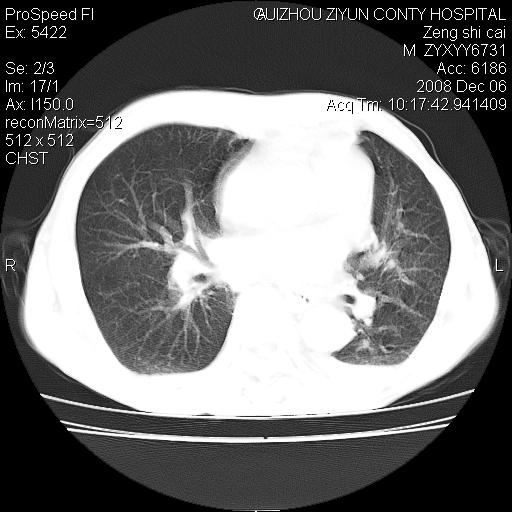

标题: CT16961:M、71岁,咳嗽半年,无血痰;胸片示右肺占位。 [打印本页]

标题: CT16961:M、71岁,咳嗽半年,无血痰;胸片示右肺占位。

右肺纵隔型肺癌伴纵隔淋巴结转移!双侧胸水!

1)考虑右肺上叶纵隔型肺癌伴纵隔淋巴结转移。2)心包积液,双侧胸腔积液。

右肺上叶纵隔型肺癌伴纵隔淋巴结转移。心包积液,双侧胸腔积液。

右肺纵隔型肺癌伴纵隔淋巴结转移!双侧胸水\\心包积液